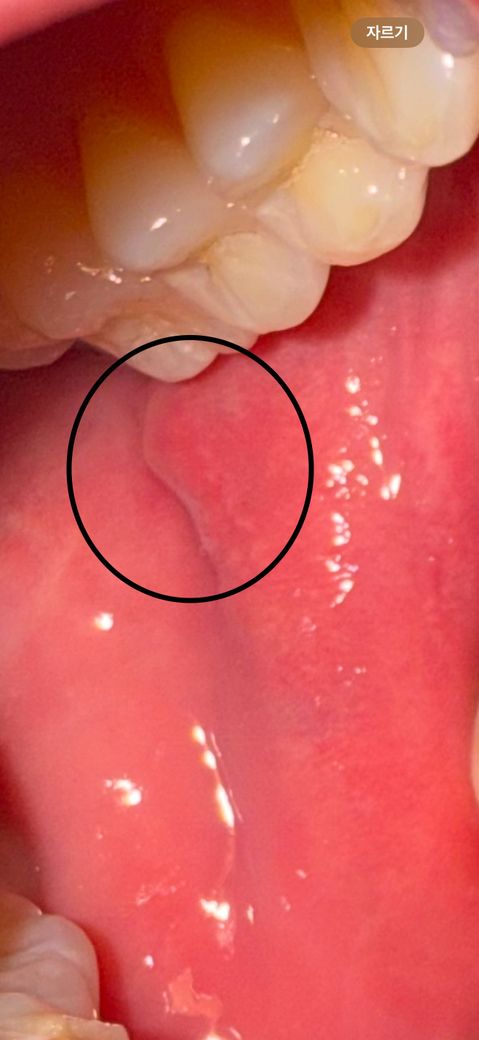

구강 양성종양 조직검사를 해봐야할까요?

사진상 보이는 입안에 한달반 정도 전에 생긴게 안 사라져서 오늘 이비인후과를 갔습니다.

선생님께서 육안으로 보시더니 염증이라고 보긴 어렵고 양성종양이라고 사라지게 하려면 시술을 받아야 한다고 하셨습니다.

사진으로 보이는 부위는 압흔으로 보입니다. 치아가 너무 강하게 물리거나 할 때 해당 부위로 조직이 말려 들어가면서 사진과 같은 앞 흔을 나타낼 수 있습니다.

이런 증상은 치아에 가해지는 힘이 줄어들면 없어지는 경우도 있습니다. 자세한 확인을 위해서 치과에서 진료를 받아보는 것을 권유드립니다.

볼살이 치아에 물려 생긴 것으며 보이며, 그냥두어도 됩니다. 양성종양 아닙니다. 식사할 때 의식적으로 볼살을 바같으로 밀어 치아에 닿지 않게 해 보시기를 권합니다. 그리고 잘때로 그쪽으로 모로 눕지 않아 보면 효과가 있습니다.